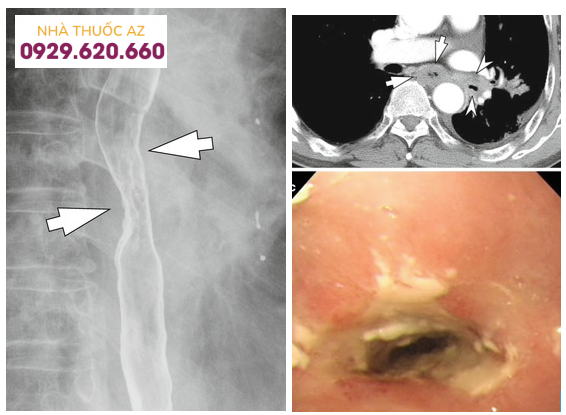

Hình 9: Hẹp lan tỏa, co thắt thực quản và vòng tròn đồng tâm (Nguồn: radiologykey.com)

Đường kính của đoạn hẹp trung bình khoảng 1cm và vị trí hẹp ở phía đoạn thực quản trên/giữa có xu hướng dài hơn so với đoạn dưới. Tùy vị trí đoạn hẹp trên chụp Baryt vẫn cần cân nhắc đến các chẩn đoán phân biệt khác. Các nguyên nhân khác gây hẹp ở đoạn thực quản trên hoặc giữa bao gồm thực quản Barrett, xạ trị vùng trung thất, sử dụng một số loại thuốc như NSAID, quinidine, trong khi hẹp ở đoạn dưới thực quản có thể do viêmthực quản trào ngược. Cần chú ý những bệnh nhân có hình ảnh hẹp thực quản trên chụp Baryt thường có triệu chứng nuốt khó và đây chỉ là một dấu hiệu gợi ý, cần kết hợp nhiều yếu tố liên quan đến bệnh sử, triệu chứng lâm sàng, hình ảnh nội soi và mô bệnh học.Vòng thực quản cũng là hình ảnh hay gặp với nhiều thuật ngữ được sử dụng như “khí quản hóa thực quản” hay “thực quản dạng vòng”. Vị trí và sự phân bố của các vòng thực quản rất khác nhau trên nội soi, có thể ở các đoạn của thực quản hoặc phân bổ lan tỏa nhiều chỗ. Đôi khi những vòng này có thể gây hẹp khiến dây sợi khó đưa qua được. Trên chụp Baryt, các vòng này thường nhiều, hay xuất hiện gần nhau, có dạng đồng tâm dọc theo lòng thực quản.

Trong những năm gần đây, có thêm một số nghiên cứu ứng dụng chụp cắt lớp vi tính hoặc siêu âm nội soi trong đánh giá VTQDBCAT. Trên chụp hình ảnh chụp cắt lớp vi tính có thể thấy dày thành thực quản. Một số hình ảnh trên siêu âm nội soi bao gồm các lớp thông thường của thành thực quản hoặc dày lan tỏa thành thực quản do tình trạng viêm và xơ hóa xuyên các lớp hoặc dày khu trú lớp cơ niêm hoặc dưới niêm mạc